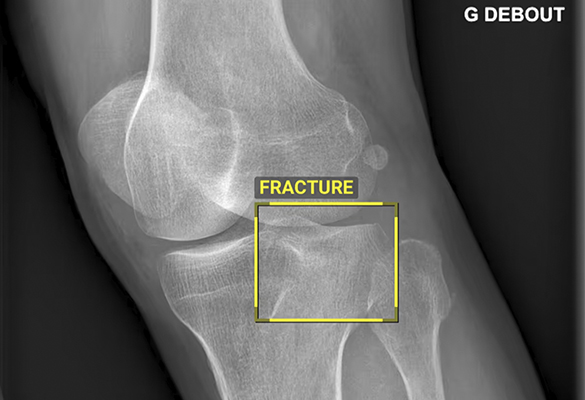

A tecnologia processa automaticamente as imagens, sinalizando zonas com probabilidade de lesões ósseas ou pulmonares. O médico pode, assim, integrar essa informação na sua observação clínica e atuar de forma mais célere e fundamentada.

O BoneView foca-se na deteção de fraturas ósseas, derrames articulares, luxações e lesões intra-ósseas, analisando radiografias em todos os utentes a partir dos 2 anos de idade.